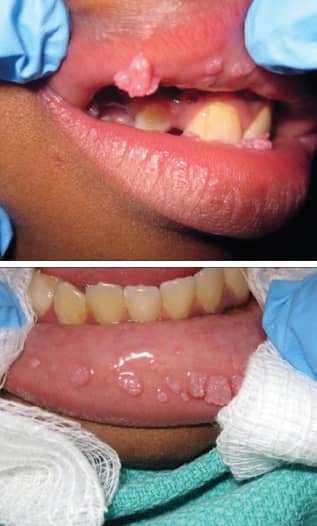

عکس زگیل لب

معمولاً در سطح داخلی لب (مخاط خیس) یا در گوشه لبها دیده میشود. اگر روی قرمزی خود لب باشد، ممکن است شبیه به زگیل معمولی پوست به نظر برسد.

-عکس زگیل لب: